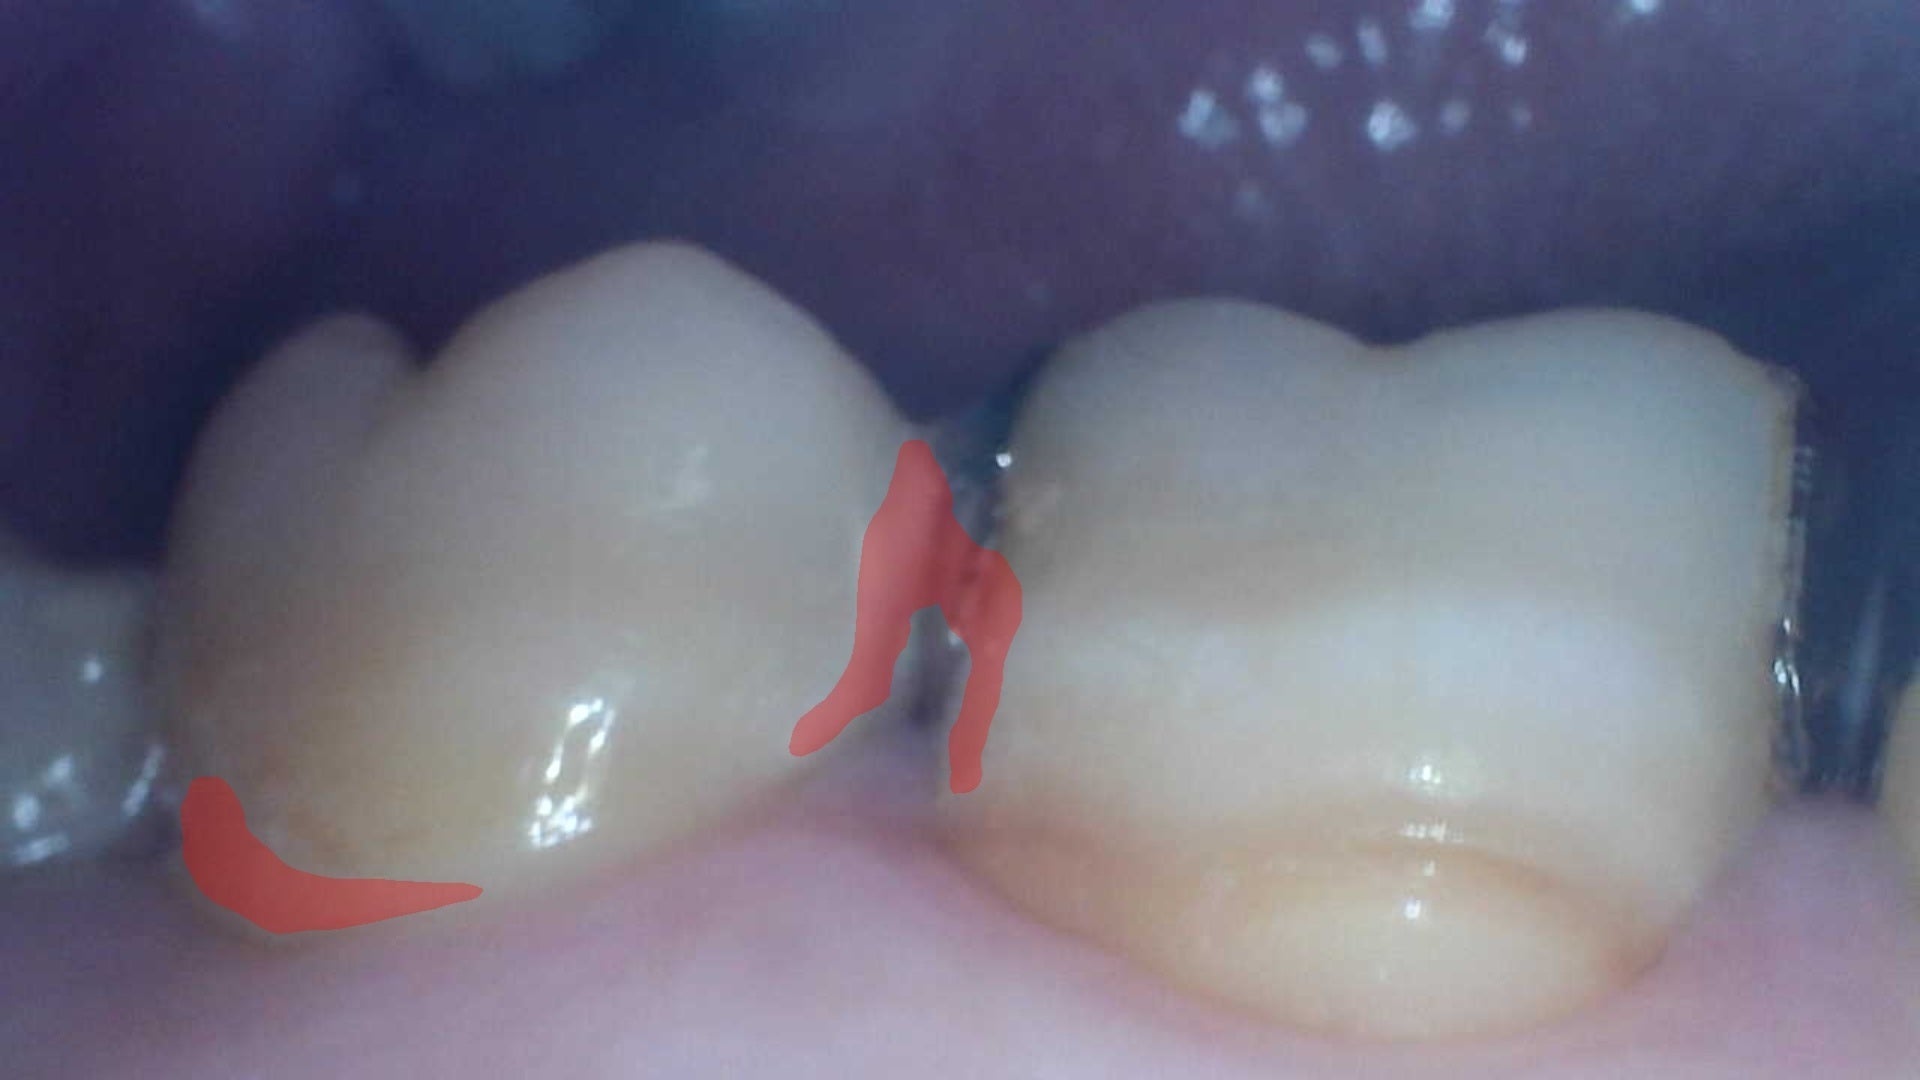

「口腔ケアサポート技術」では、専用口腔内カメラを使用して自身で撮影した口腔内画像を画像認識AIサーバーへ送信すると、画像認識AIが汚れ付着箇所を認識し着色を行います。

なお本活動では、口腔内画像を1000枚以上収集して画像認識AIを構築し、本AIによる汚れ発見の精度はIoU0.421(※3)です。

※3.IoU(Intersection over Union)は、物体検出やセマンティックセグメンテーションにおいて、正解の領域と予測の領域の重なりをあらわす精度指標。